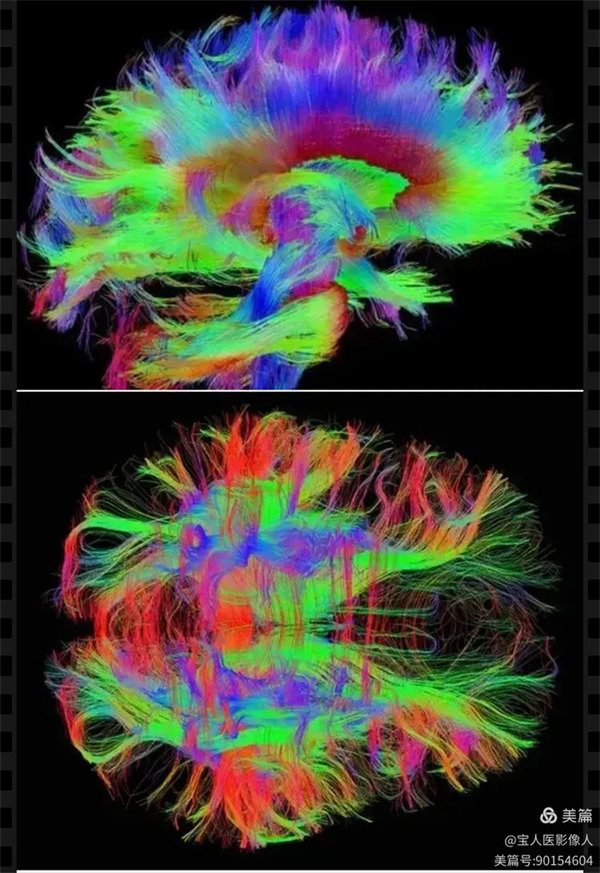

病例20:患者,中年女性,外院發現腦病變,來寶雞市人民醫院神經外科就診,進行了顱腦磁共振彌散張量成像(DTI),獲得腦神經纖維束圖像(DTT)以及多種定量參數值,為疾病的鑒別診斷、診斷分級以及手術路徑選擇提供了定量信息。

圖1:DTT圖(側位)

顱腦主要的神經纖維束顯示,左側額頂部病灶周圍神經纖維素顯示異常。

圖2:DTT圖(正位)

顱腦主要的神經纖維束正面觀。

病灶周圍神經纖維束受壓弧形移位,呈抱球樣。

為了獲得腦神經纖維束高清、完整的顯示,醫學影像科張軍暉副主任醫師和畢國強主管技師決定選擇更復雜,更耗時間(常規四倍)的序列掃描。隨后在ADW4.6工作站耗多時處理出顱腦高清DTI圖像和病灶的各種參數值,為病變的定性,定位,定量提供了重要信息,也為神經外科團隊精準的,完整的切除血供極其豐富的病變組織,提供了非常重要的手術前決策價值。最終,多模態磁共振技術應用,綜合多種定量參數,影像診斷(病變類型、分型、分級)與術后病理結果完全一致。